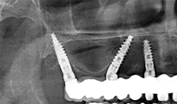

Narrow-diameter implants (NDIs) can be placed in edentulous areas with very thin residual ridges but sufficient bone height.10,19 Also known as small-diameter implants (SDIs) or mini-implants, NDIs have diameters less than 3.5 mm (typically 1.8 mm to 2.9 mm), with various lengths.20 The surfaces of NDIs are blasted and acid-etched to increase roughness and surface area. These implants also often have microthreaded transgingival collars to facilitate soft-tissue adherence.21 The tips of NDIs are often sharp or slightly blunted to provide self-tapping and bone compression capabilities when inserted through the medullary bone. Variable thread thickness and spacings allow for the delivery and use of the implants in the different bone densities present throughout the mouth.20 Square, rectangular, or o-ball implant head designs are utilized to retain both fixed and removable restorations.21

Notably, multiple short and narrow-diameter implants can be placed and splinted together to restore both partially and completely edentulous maxillary arches.9,10,16,19

Fig 2. Use of multiple small-diameter one-piece implants to restore a thin edentoulous maxillary arch without grafting.

Figure 2